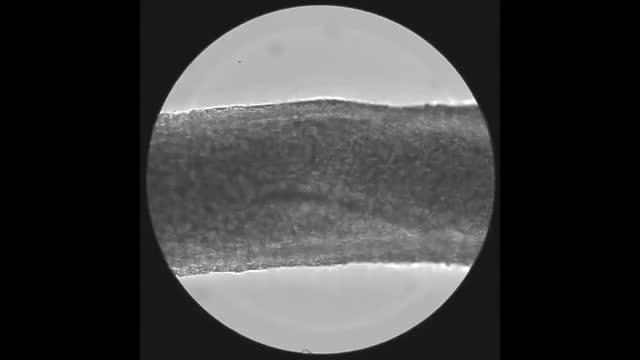

video: Video recording of the spontaneous contractions of a lymph vessel during perfusion with MWCNTs. The spontaneous contraction of the vessel wall during perfusion with MWCNTs (1.0 mg/mL) is in synchrony with the flow of black MWCNT nanoparticles. The MWCNTs in the vessel move faster in the front and back of the valve with vessel contraction, and particles flow beyond the valve during dilation. In both cases, the valve was observed to move across the center of the lymph vessel.

Image: